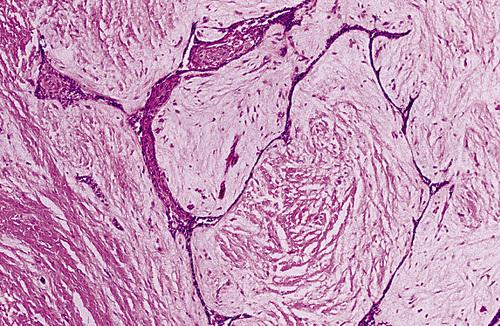

- This photomicrograph shows a thin epithelial lining with focal nodular thickenings of clear cells.

- These thickenings often show a swirling appearance of the glycogen-rich clear cells.

lateral periodontal cyst